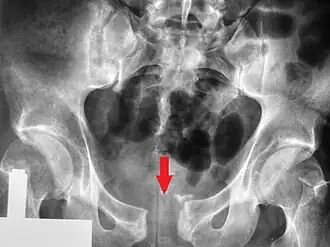

Radiologie standard

De nombreuses incidences radiologiques ont été évaluées par le passé. Une incidence de face du bassin est la première radiographie à réaliser dès l’admission d’un patient pour lequel on suspecte une lésion de l’anneau pelvien. Les radiographies standards révèlent 90 % des fractures du bassin[3].

Différentes incidences obliques sont indiquées en cas de suspicion de fracture du bassin non objectivable sur la radiographie de face. En en cas de suspicion de lésions particulières (fracture isolée du sacrum, fracture du cotyle…) des radiographies spécifiques peuvent être demandées.

Scanographie

Le CT-scan a pris une place considérable dans l’imagerie des traumatismes du bassin. Il est devenu possible d’obtenir des reconstructions en 3D permettant une meilleure visualisation anatomique avec évaluation des saignements dans le péritoine ou le rétropéritoine. Il permet aussi de confirmer une dislocation de hanche avec fracture du cotyle[10],[11].